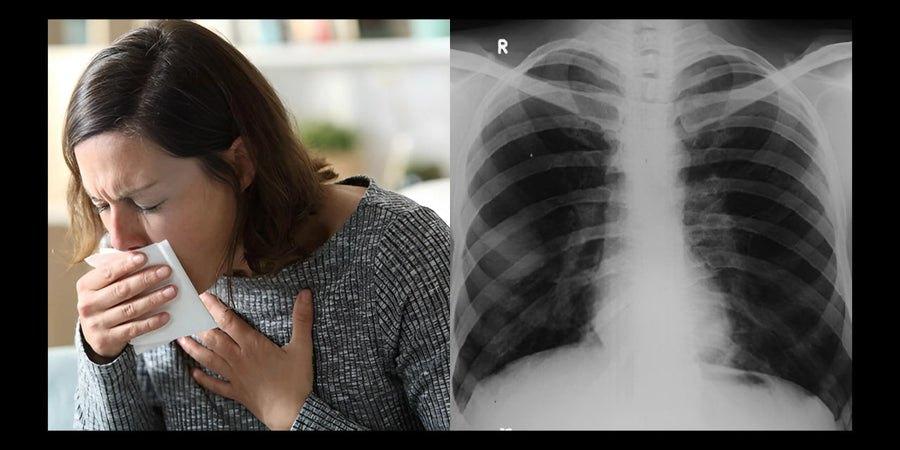

How I went from shortness of breath and coughing to breathing easily

Are you often short of breath, have a cough or feel that your lungs are not functioning optimally? Even though your doctor...

The natural recovery of 'phagocytes' relieves breathing difficulties in COPD within a few weeks

How to Treat Bronchitis Naturally

How I finally succeeded in getting rid of my bronchitis after four years and strengthened my bronchi - completely naturally and without...

Beyond Quitting Smoking: How I Removed Years of Toxic Mucus From My Lungs